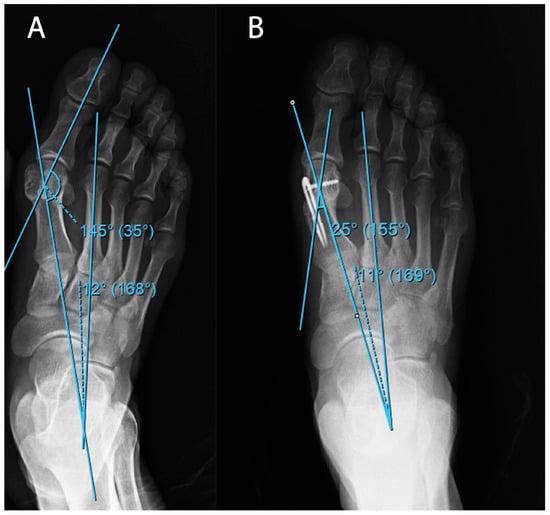

Patients with results indicative of osteoarthritis and gout and those who could not adhere to routine clinical follow-ups were not included. Patients in Group 1 to whom the self-locked intramedullary platter was administered were observed for 5 (3–12) months, while patients in Group 2 to whom the Herbert screw was administered were observed for 14 months (8–30). During the postoperative period, short leg splints were administered only to patients in Group 2 for 4 weeks. A total of 18 feet from 12 patients were fixed using an intramedullary platter and another 18 feet from 12 patients were treated using Herbert screw (Figure 2).

Figure 2. An example of (A) preoperative and (B) postoperative radiographic examinations of patients in Group 2.